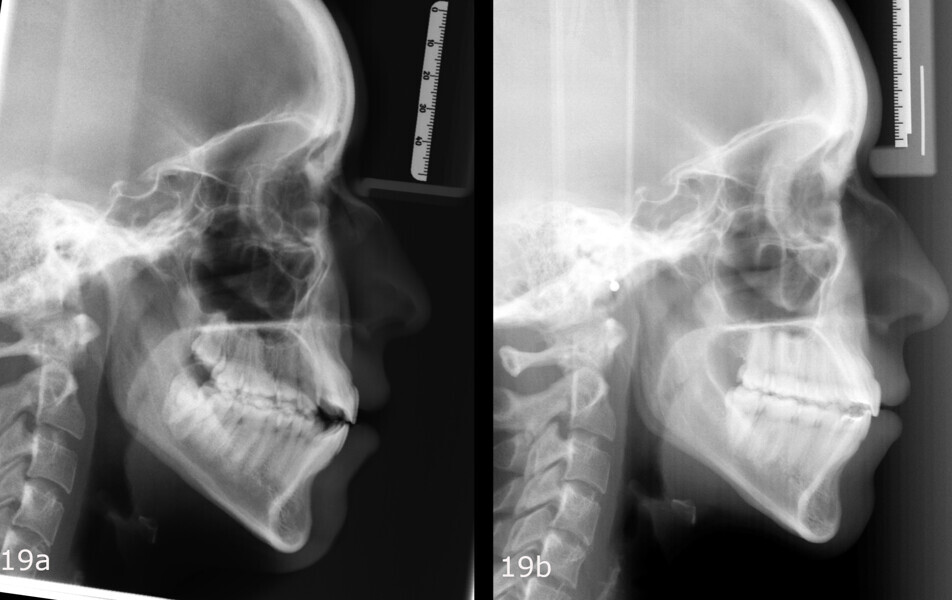

The 23-year-old dolichofacial female patient complained of not being able to chew properly. Facial examination showed a convex profile, an enlarged lower facial height, and a skeletal Class III malocclusion (Figs. 1–3). Intra-oral examination revealed an Angle Class III right subdivision malocclusion, anterior open bite, no overjet and a maxillary dental midline deviated about 3 mm to the right compared with the mandibular dental midline (Fig. 4). The panoramic radiograph confirmed previous extraction of the maxillary right first premolar and the presence of all four third molars (Figs. 5 & 6).

The treatment objectives included closing the anterior open bite, achieving a bilateral Angle Class I relationship and a proper overjet and overbite, correcting the midline discrepancies, and achieving a profile harmonisation. The treatment plan consisted of orthodontic camouflage treatment with asymmetric distalisation in three of the four quadrants using Invisalign aligners (Align Technology) and third molar extraction. The Invisalign Comprehensive package was chosen, and 63 pairs of aligners were used (Figs. 7–10). Each aligner was worn for 20 hours a day for one week each. The use of Class III elastics on both sides was indicated. Afterwards, ten refinement aligners were needed to improve the interdigitation on the right side (Figs. 11 & 12).

Although Class III elastics tend to extrude the maxillary molars and generate clockwise mandibular rotation, aligners allow us to prevent these complications, since we have better control over tooth movement, enabling us to counteract unwanted dental movements. In this case, an intrusion of the posterior teeth was planned, which would generate anticlockwise rotation of the mandible in an anticlockwise direction. This vertical control led to the closure of the anterior open bite and the reduction of the lower facial height, thereby improving the facial profile.

The total treatment time was 15 months. An Angle Class I relationship was established along with adequate anterior and canine guidance, establishing a functional occlusion. This not only ensures optimal masticatory function but also protects the teeth and the temporomandibular joint from excessive force. Maxillary and mandibular fixed retention were installed at the end of the treatment (Figs. 13–19).